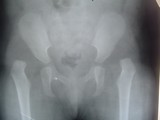

Pre-operative radiograph of dislocation of hip joint